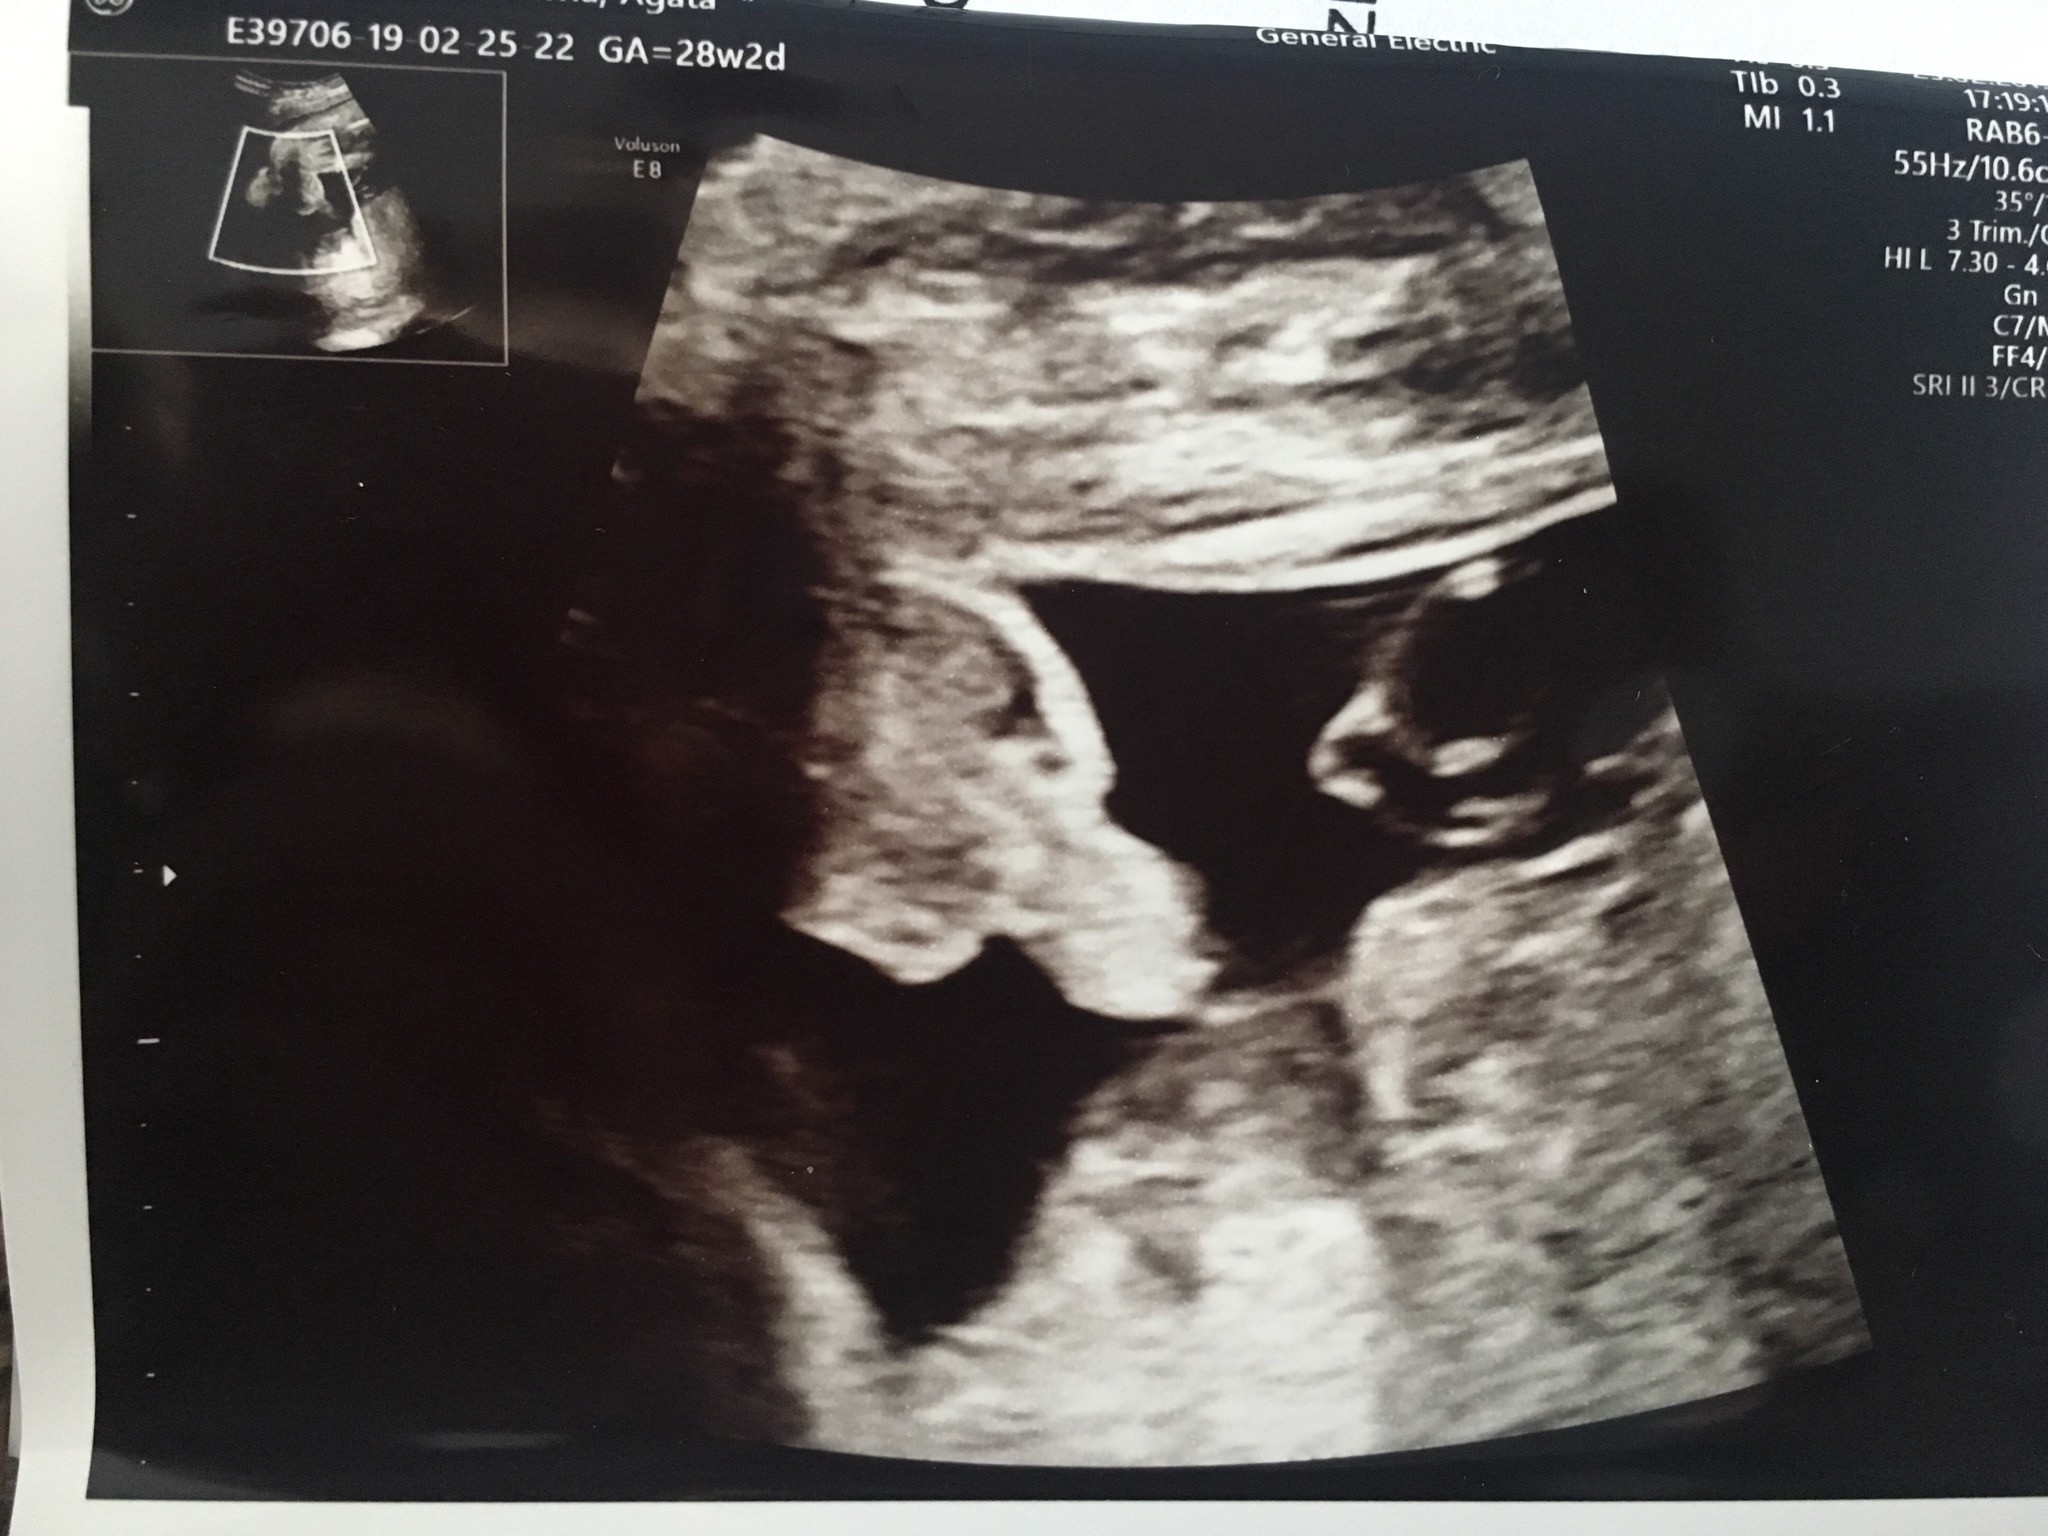

Witam w 19 tygodniu ciąży dowiedziałam się ze będę miała dziewczynkę w 20 tyg okazało się jednak , że to chłopak. Sama już nie wiem bo na jednym usg widać na pewno dziewuche a na drugim chłopca. Może to pempowina ?? Może ktoś mi pomoże rozwiązać ta zagadkę

Załączniki

• 4A8F5FF1-76CA-4DE0-AC12-5EDF08E820F2.jpg

4A8F5FF1-76CA-4DE0-AC12-5EDF08E820F2.jpg

596,4 KB · Wyświetleń: 44 156